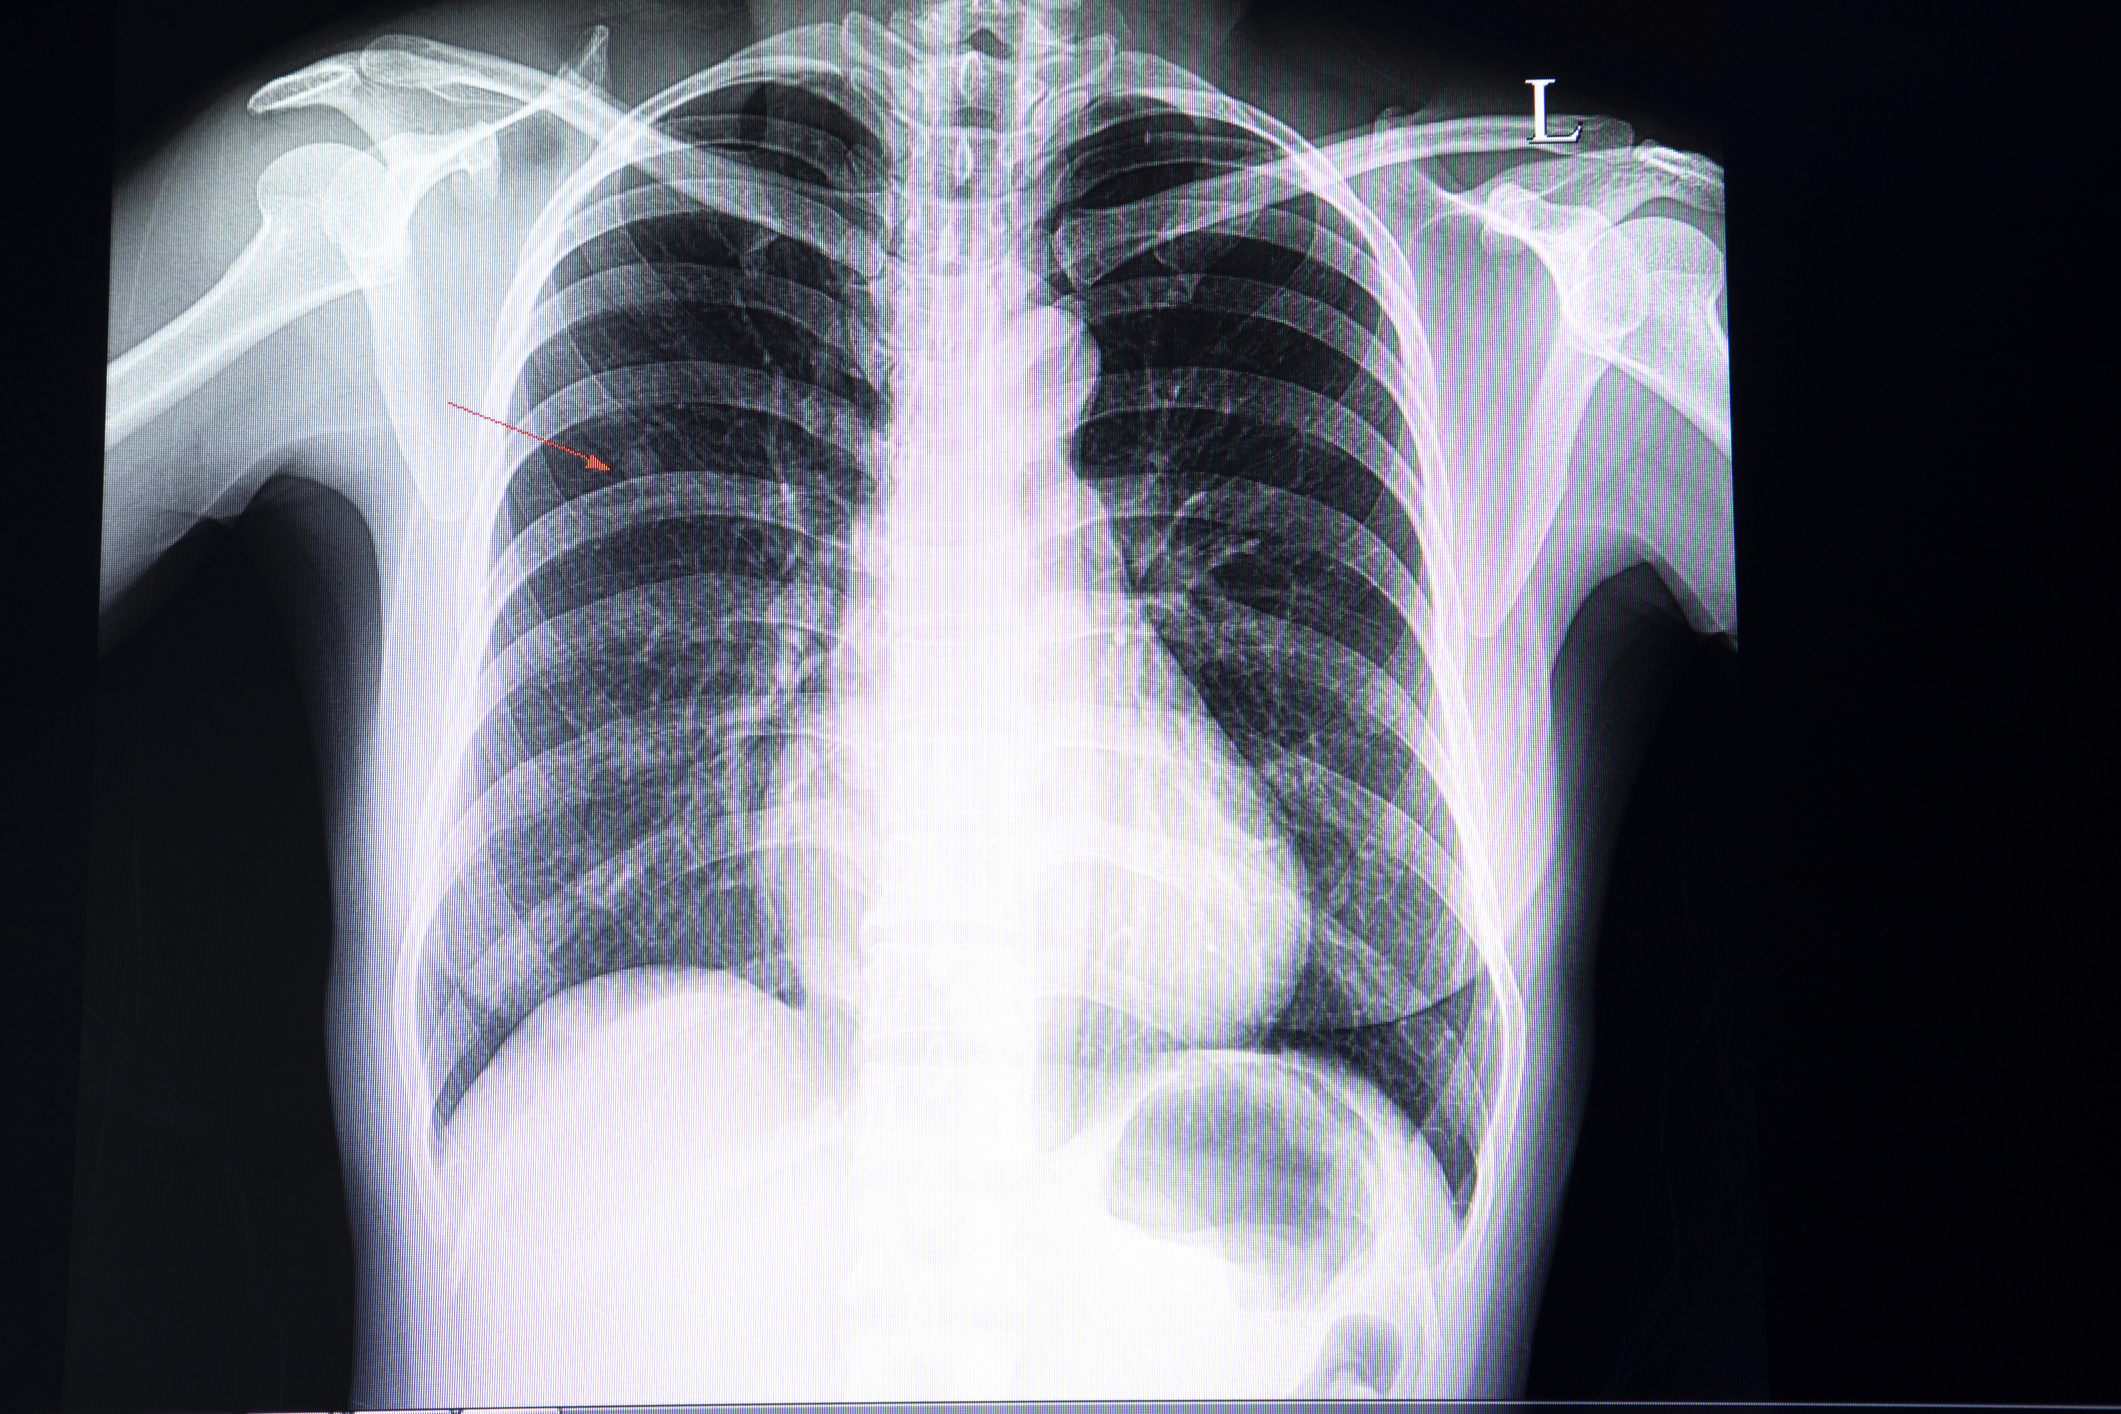

肺部結節聽起來似乎也很嚇人,但出現肺結節是否代表患癌?不一定!其實肺結節演變成惡性腫瘤的機會很低,超過9成的肺結節均屬良性,即使大於8mm結節的癌變機率亦只有約3%。不過,由於結節越大,病變機率越高,因此仍需要定期觀察結節,及早發現是否有變大或惡化跡象。

在肺結節的引發因素中,吸煙與肺結節是否有必然關係?其實不一定!吸煙者與非吸煙者同樣有患肺結節的風險,但需要注意的是,兩者所得肺結節的性質可能不同:吸煙者大部分患「實性肺結節」(solid nodule),非吸煙者大部分患「磨玻璃肺結節」(ground glass nodule)。

「實性肺結節」增長速度較快,甚至有機會一年內演變成中期或晚期肺癌。如患者適合進行手術,建議越早切除越好。「磨玻璃結節」發展速度一般較慢,無需急於手術,定期監察結節大小即可。